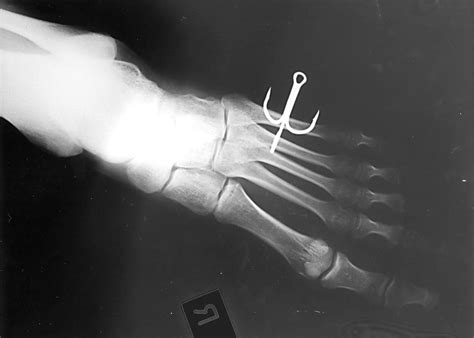

Francis Vasquez Blog